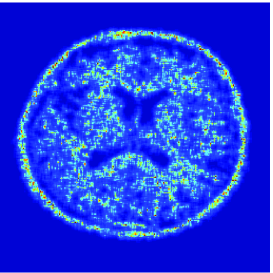

At this point, it may be interesting to compare the proposed extension with the approach developed in [24]. The use of the Anscombe transform [2], in [24] is actually tantamount to approximating the anti log-likelihood of the Poisson distribution by

The proposed quadratic extension is illustrated in Fig. 4 where a graphical comparison with the Anscombe approximation is performed.

Here, is a uniform blur with . A () medical image shown in Fig. 5(a) is degraded by and corrupted by a Poisson noise following the model described in the previous section for various intensity levels. The degraded image is displayed in Fig. 5(b) when .

To evaluate the performance of our algorithm we use the Signal to Noise Ratio defined in Section 5.3.2. Tab. 2 shows the values of the obtained for different values of and . As predicted by Proposition 5.4(v), beyond some value of , which is dependent of , the optimal value is found. We also compare our results with those provided by two different approaches. The first one is the regularized Expectation Maximization (EM) approach (also sometimes called SMART) [10, 31] where the Poisson anti-likelihood penalized by a term proportional to the Kullback-Leibler divergence between the desired solution and a reference image is minimized. Its weighting factor has been adjusted manually so as to maximize the and, the reference image is a constant image whose pixel values has been set to the mean value of the degraded image. The other approach is the method based on the Anscombe transform proposed in [24] and discussed in Remark 5.6. For fair comparisons, the method here employs the same orthonormal wavelet representation, the same functions as ours and the same constraint set . It can be observed that the approach we propose gives good results. However, for high intensity levels (), the method based on the Anscombe transform performs equally well in terms of SNR. The restored images are shown in Fig. 5, when and after 3000 iterations. In spite of an important degradation of the original image, it can be seen that our approach is able to recover the main features in the image. It can also be noticed that the image restored by the two methods exhibit different visual characteristics.

![]() |

| (b) | (c) |

| (d) | (e) |